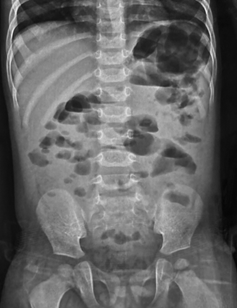

In paralytic ileus, there is too much gas in both small and large bowels (Figure 4 & 5).

Figure 4 Anteroposterior supine abdominal radiograph in a 4-year-old child showing multiple dilatated bowel loops scattered throughout the abdomen haphazardly with presence of gas in the rectum suggestive of paralytic ileus.

In paralytic ileus there is uniform dilatation of bowel to the level of the rectum (Figure 4 & 5).

In paralytic ileus, there are few and less dilated air fluid levels scattered throughout the abdomen (Figures 4 & 5).

In paralytic ileus, the loops are scattered disorderly throughout the abdomen (Figures 4 & 5).